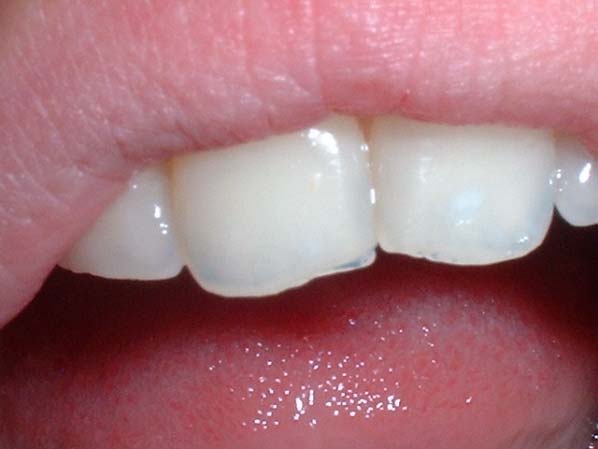

Another useful aid is to move a gloved finger behind the upper incisor teeth tips looking for translucency.

Gloved finger test